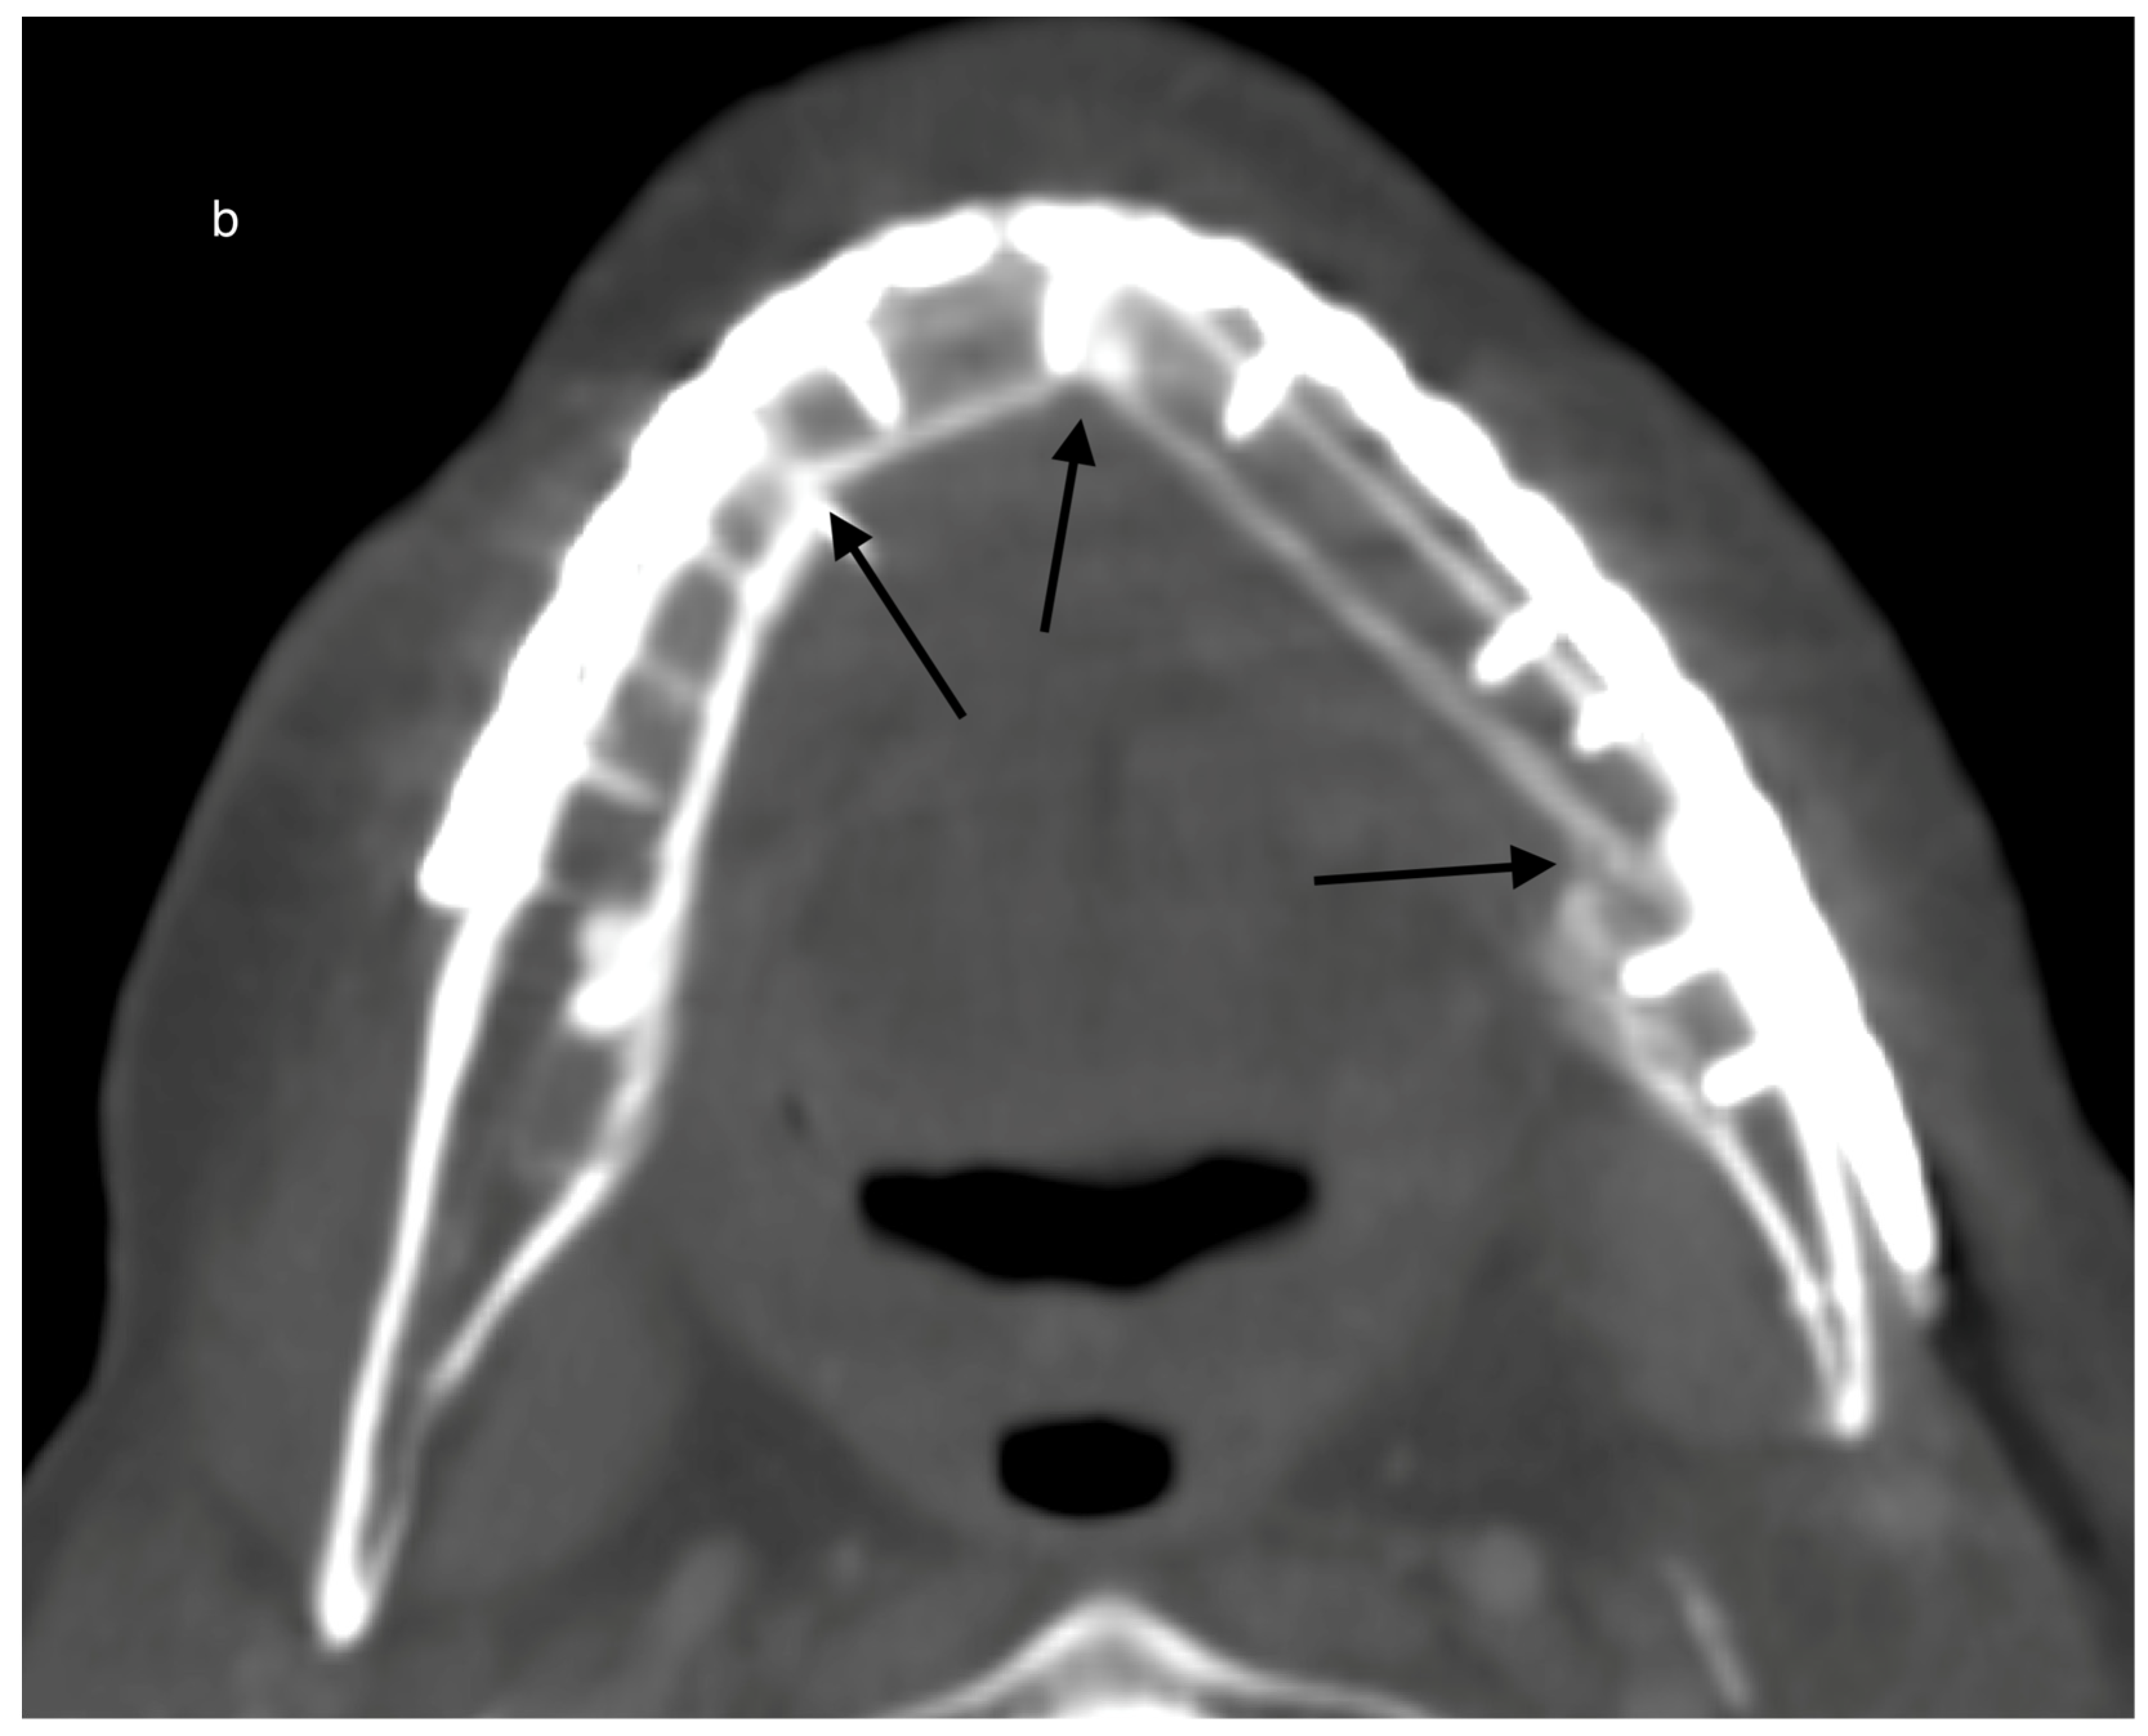

| HU gain overall for grouping locations horizontally #1 per day (p = 0.003) | ||||

| basal | reference | |||

| cranial | 5.26 | −53.34 | 63.86 | 0.860 |

| middle | 114.06 | 45.35 | 182.76 | 0.001 |

| HU gain overall for grouping locations vertically #2 per day (p = 0.005) | ||||

| Vestibular (+) | reference | |||

| Lingual (*) | −98.72 | −157.31 | −40.13 | 0.001 |

| Middle (#) | −86.70 | −155.41 | −17.99 | 0.013 |